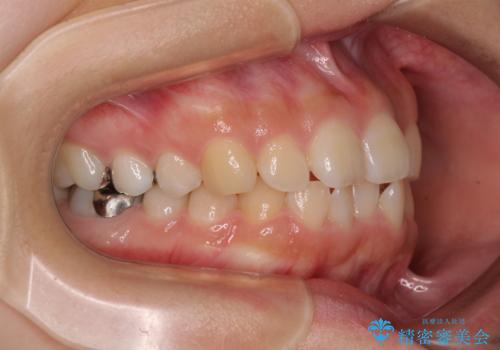

- 前歯のクロスバイトと口元の膨らんだ横顔の印象を気にして来院された患者様です。

レントゲン写真の分析結果からは、それほど口元が突出しているという結果にはなりませんでした。

しかしながら、唇を閉じたときに口元に緊張感があり、そのまま叢生を解消すると横顔が突出した印象になる可能性が高かったため、上下左右の小臼歯4本を抜歯して、ワイヤー装置にて矯正治療を行うこととしました。

矯正治療後には、目立っていた奥歯の銀歯をオールセラミッククラウンへ作り替え、スッキリした口元に仕上がりました。